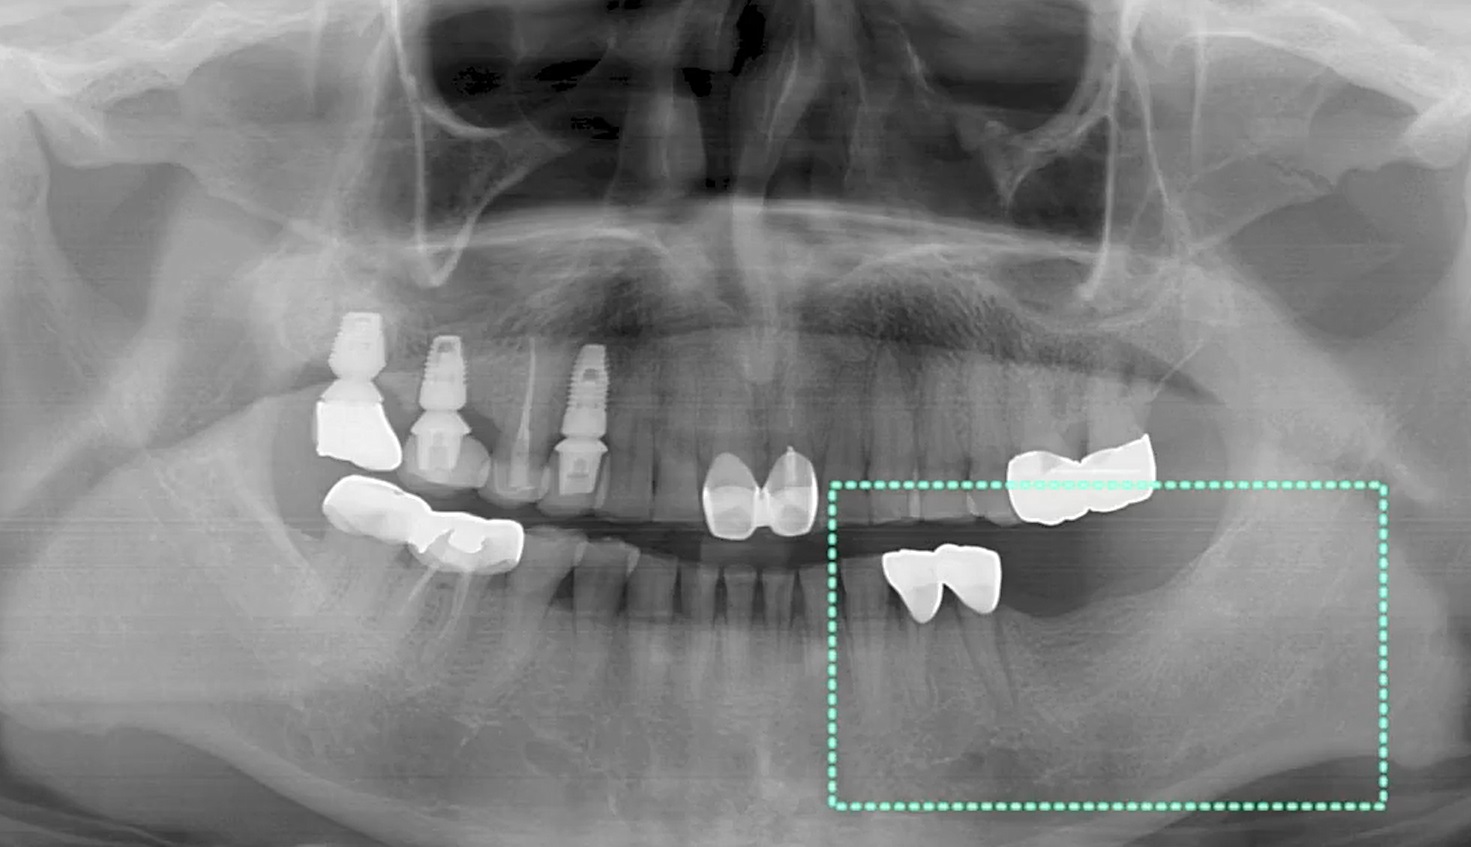

Root Membrane with R2GATE

#12,#21,#23,#26,AnyRidge,Digital Guided Surgery,Dr. Konstantinos Siormpas,Flapless,Guided surgery,Immediate Placement,Maxillary Anterior,Maxillary Posterior,R2GATE Guide,R2GATE Universal Kit,Root Membrane,Root Membrane Kit,video,Xpeed